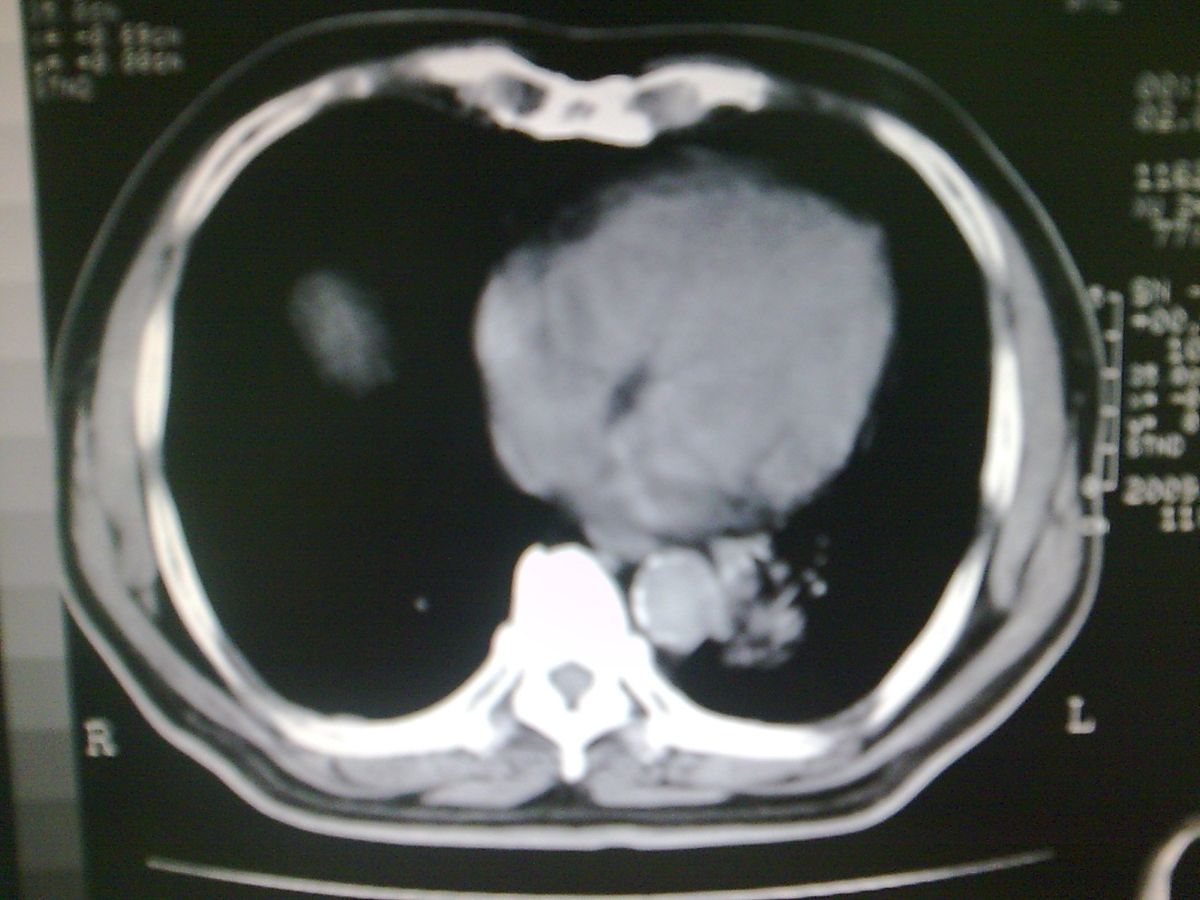

标题: CT19282:男性,70岁,咳血, [打印本页]

标题: CT19282:男性,70岁,咳血,

图片少了些,考虑周围性肺癌

考虑周围性肺癌

周围型肺癌。

考虑左下肺周围性肺癌。

肺隔离症不除外建议增强扫描

考虑左肺下叶周围型肺癌可能。